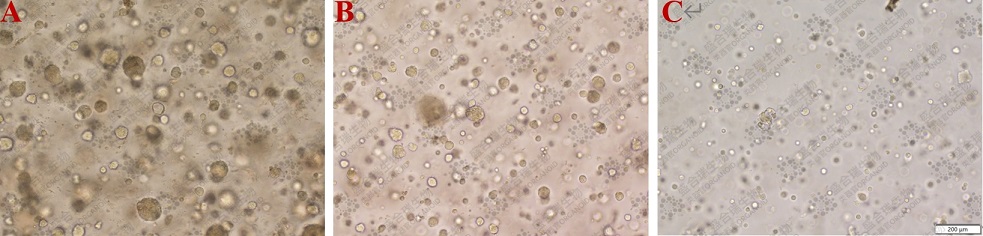

图1. 前列腺癌类器官原代培养、传代和复苏后的生长状态例图。(A)原代前列腺癌类器官的生长状态(P0)。类器官呈泡状和实体混合结构,大小约100μm。(B)第一代前列腺癌类器官的生长状态(P1),传代后的类器官仍为泡状和实体混合结构。(C)复苏后的类器官表现出稳定的增长趋势。比例尺:200 μm。